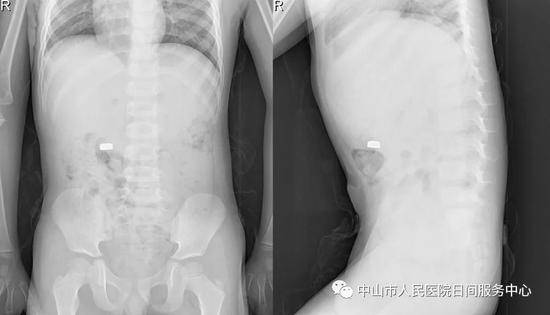

Người mẹ sau khi nghe con nói thì hốt hoảng đưa con trai đến Bệnh viện nhân dân thành phố Trung Sơn để điều trị, một vị bác sĩ Nhi khoa ngay lập tức yêu cầu đưa cậu bé đi chụp X quang ổ bụng, kết quả cho thấy hình ảnh chiếc pin điện tử đang bị mắc kẹt trong khoang bụng.